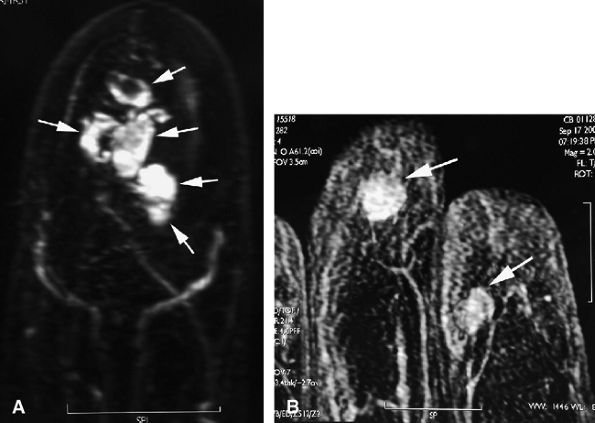

Nodular or tubular enhancement may be seen after gadolinium administration. MRA is complementary to standard MR studies, providing precise details of the angiographic appearance of the malformation (Fig. 11.78). MRA of the fingers is technically challenging because of the small caliber of blood vessels and their changing orientation. The MRA technique that is most suited to the fingers is a 3D coronal acquisition after gadolinium administration. This rapid technique (requiring less than 30 seconds for acquisition) yields high spatial resolution and is not dependent on vessel orientation. Injection of a gadolinium test dose allows precise determination of maximum arterial enhancement.180 Temporal resolution remains inferior to DSA.4

FIGURE 11.78 ● Venous malformation. (A) Axial post-contrast fat-suppressed T1-weighted image showing vascular malformation invading the fourth intermetacarpal space and the fifth metacarpal (arrows). (B) MR angiogram of multifocal vascular malformation with a distal extension toward the lateral aspect of the fifth finger (arrows).